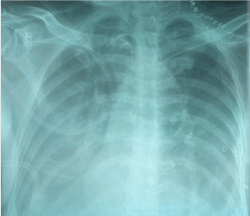

Following surgery patient was allowed with Ryles tube feeds from POD-1. On POD 3 patient developed tachypnea, chest pain, and fever with respiratory difficulty. His chest x ray showed bilateral pleural effusion with collapse of lungs (Figure 1). Ultrasonography revealed gross pleural effusion on both sides. However, compression ultrasound of both lower limbs did not reveal any features of deep vein thrombosis (DVT).

Figure 1. POD 3 CXR showing massive plural effusion (R>L).

Pleural tap was performed with underwater seal on both sides. On first day 1150 ml of white turbid fluid was drained from the left side and 750 ml on right side. Biochemical analysis of the fluid was suggestive of chyle. However, his neck drains did not show any Chylous leak. Next day, 600 ml of Chylous fluid was drained from both sides. Patient was kept on strict fat free diet. There was marked improvement in the respiratory symptoms and his chest X-ray after two days showed clear lung fields with minimal blunting of bilateral costophrenic angles (Figure 2). Ultrasonography after fifth day did not reveal any fluid in bilateral pleural spaces. Both the neck drains were removed on POD 7. Patient had no pulmonary sequelae.